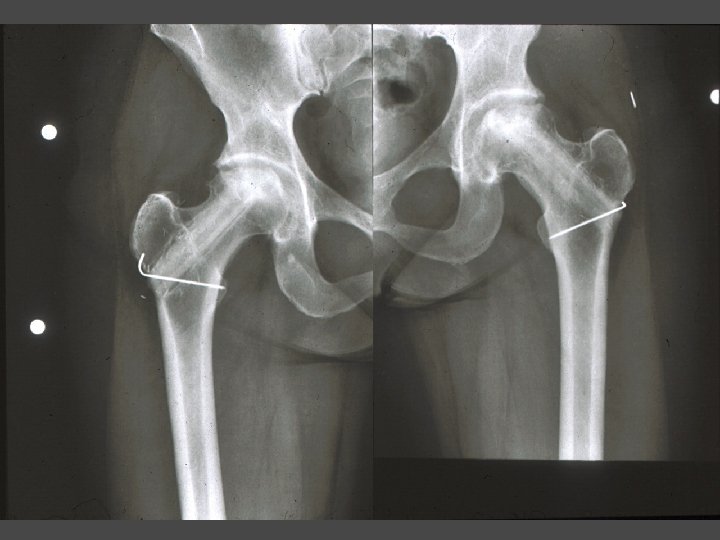

OSTEONECROSIS-THA Technical Considerations • Select implant using same criteria as for other Dx • Do not overream socket • Watch for socket fx • Augment socket fixation with screws • Choose femoral component depending on metaphyseal bone changes from previous surgery